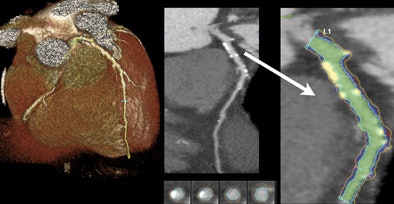

| Calcium can be readily identified on contrast-enhanced coronary CTA. After selecting an arterial segment with a software tool and making any necessary adjustments, the volume of high-intensity calcium can be measured. The calcium volume is converted to the Agatson score with a standard linear conversion factor. All images courtesy of James Otton. |

They identified calcifications by windowing and examining each axial slice in minimal slice thickness, as well as thick maximum intensity projection (MIP) and curved multiplanar reconstruction (MPR) views, Otton told AuntMinnie.com.

If an area of possible arterial calcification was seen, the calcium-containing arterial segment was selected in curved multiplanar view utilizing the SurePlaque plaque quantification software (VitreaFX v3.1, Toshiba).

The quality of automated arterial edge detection was also visually examined in arterial cross section reconstructed at 1-mm intervals along the arterial segment and was manually adjusted, as necessary, to include calcium deposits within the vessel wall and exclude luminal contrast.

The SurePlaque tool was adjusted to quantify the volume of high-intensity voxels exceeding 320 HU within the selected areas. The final Agatston calcium score estimate was obtained by multiplying the measured calcium volume by the empiric conversion factor.